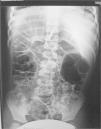

Se realiza Rx abdominal (fig. 1) que se compara con una previa (fig. 2) realizada 4 años antes con ocasión de otro episodio de dolor abdominal; ambas muestran una imagen similar.

La anormal distribución de aire en hemiabdomen derecho con aparente interposición del colon entre hígado y diafragma presente en ambas radiografías, junto con la clínica de dolor abdominal intermitente nos llevó a hacer el diagnóstico de síndrome de Chilaiditi. Su tratamiento conservador, basado en una alimentación equilibrada y rica en fibra, ha evitado nuevos episodios en nuestro paciente.